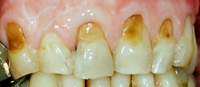

Die Abb. 1 bis 4 sollen als anschauliche Beispiele für gesunde und kranke Fundamente dienen.

Dass die Zahnputztechnik wichtig ist, möchten wir anhand eines Beispiels zeigen. Durch jahrelange falsche Zahnputztechnik hat ein Patient sein Zahnfleisch auf der einen Oberkieferseite (Abb. 5) richtiggehend zurückgeschrubbt (Zahnfleischrezession). Zudem ist im Zahnhalsbereich (Abb. 6) viel gesunde Zahnhartsubstanz weggefegt worden (keilförmige Defekte). Es wundert darum kaum, dass so freiliegende Zahnhälse empfindlich weh tun können. Auf der Oberkiefergegenseite sind Zähne und Zahnfleisch gesund geblieben und wir sagen Ihnen auch warum (kleiner Tip: mit welcher Hand putzen Sie Ihre Zähne?). Unter dem Kapitel Mukogingivalchirurgie erfahren Sie, ob und wie solche Zahnfleischverluste therapierbar sind.